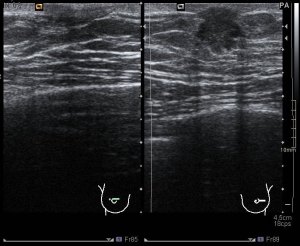

La imagen 5 y la imagen 6, sin y con doppler, para estudiar vascularización del tejido mamario patológico. No existe claro nódulo, por tanto no medimos. Por contra en la imagen 7,8 y 9 que te pongo a continuación puedes observar un claro nódulo retroareolar de la mama masculina, que tiene este aspecto semiológico:

En mama izquierda coincidiendo con la palpación del paciente, existe un nódulo retroareolar sólido de contorno irregular con vascularización redondeada que mide 11 mm.

Los ganglios axilares eran normales.

BIRADS 4C. Se cita al paciente desde servicio radiología para BAG con control ecográfico en mama izquierda.

Con resultado de AP positivo para Ca de Mama.